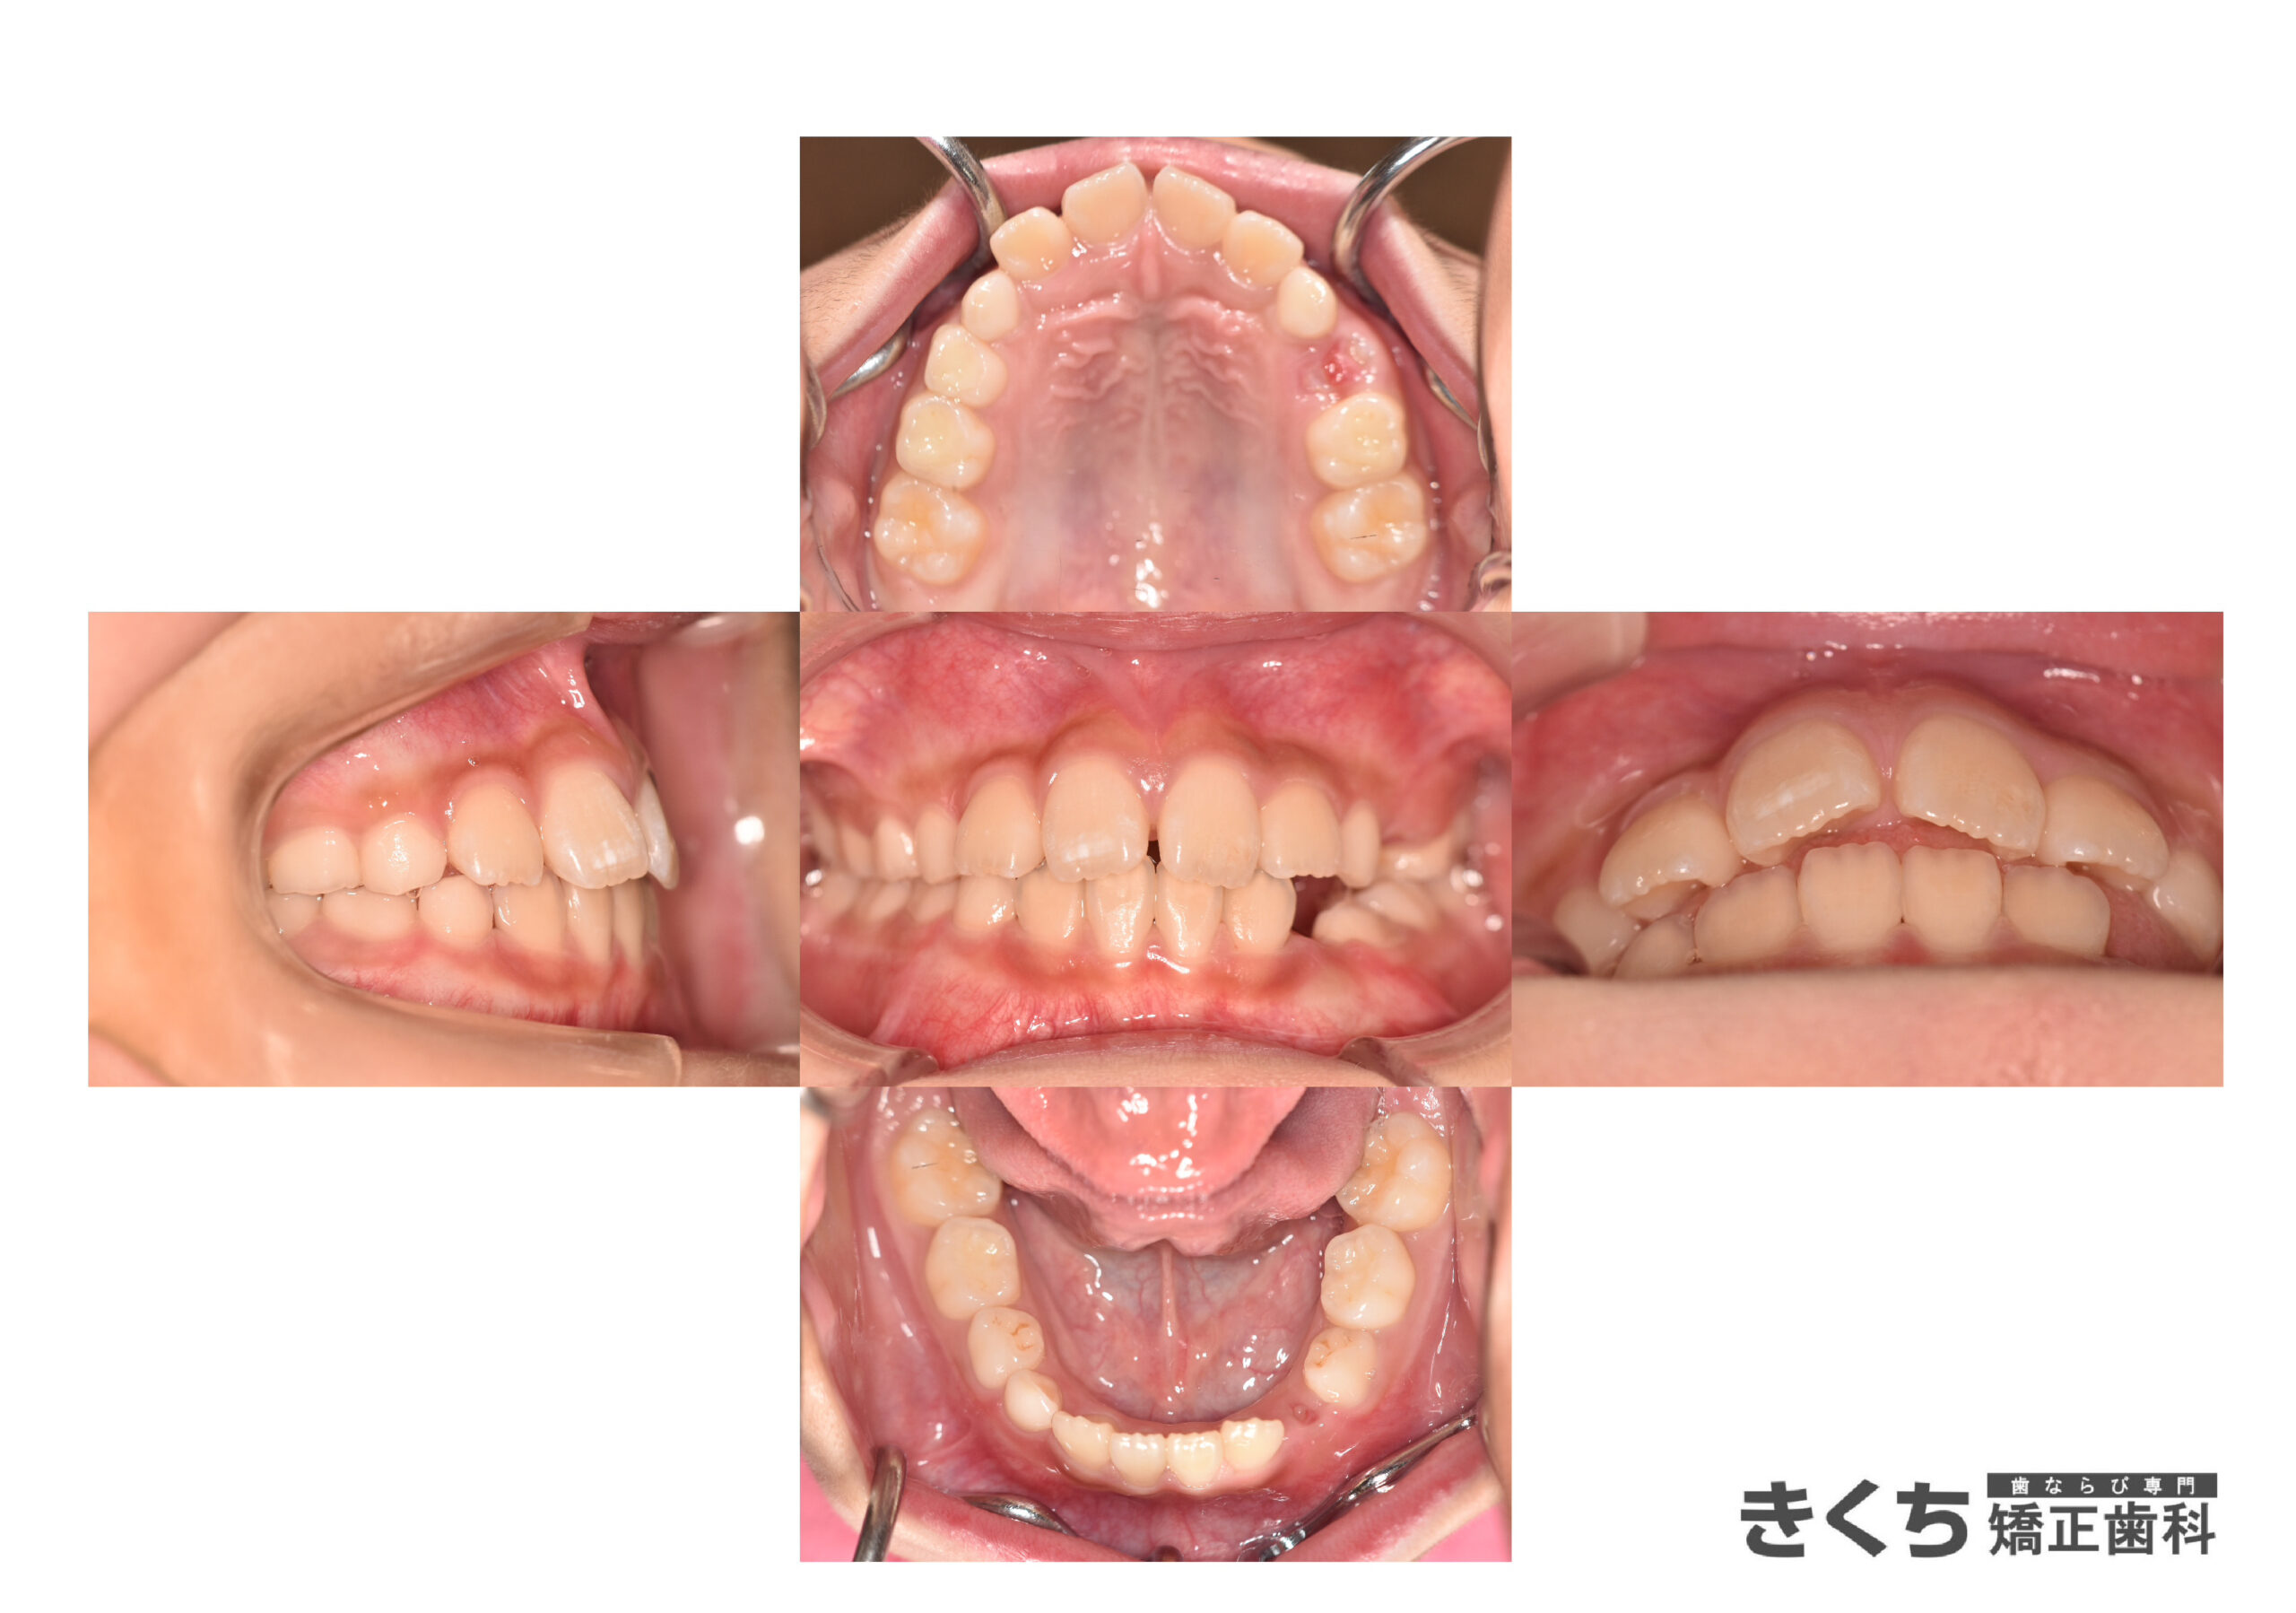

↓↓↓↓↓↓↓ 6ヶ月後

口腔筋機能 の改善だけで、気にしていたかみ合わせが自然に改善しました。